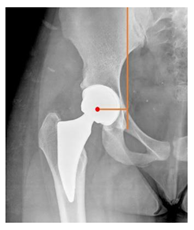

Postoperative radiographs showed a significant vertical malposition of the cup in 1 case (1.4%), a significant varus stem in 8 cases (10.8%) and a significant valgus stem in 1 case (1.4%). Two patients (2.7%) showed moderate heterotopic bone formation (Brooker ≥ 2), that did not significantly affect the hip motion and symptoms. All those THR that did not undergo revision showed good radiographic osteointegration, with no evidence of implant breakage, radiographic lucencies, bone defects, cup migration, or stem subsidence at the most recent radiographs.

In our experience, implant malposition was the only reason for implant revision. In one case, progressive subsidence was observed in a varus undersized stem, implanted in a boy with Albers–Schömberg disease; in another case, an excessively vertical cup with a 28 mm femoral head caused hip instability and required cup revision.